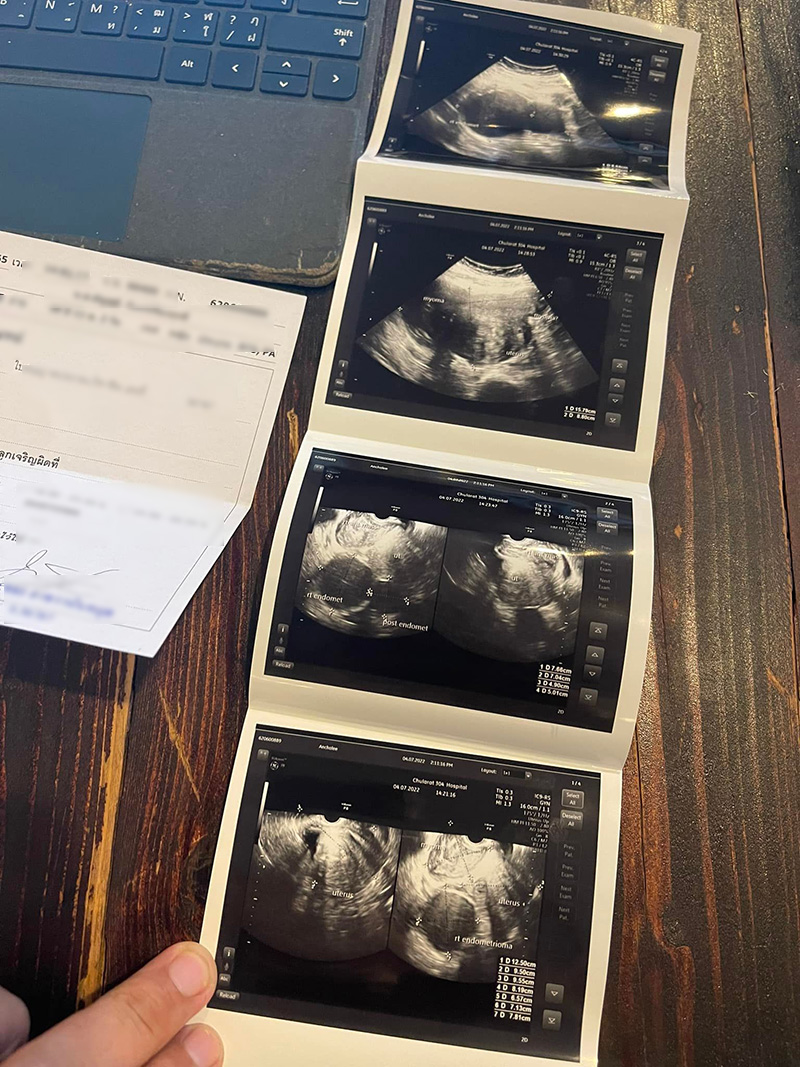

สิ่งที่พบ คือ ช็อกโกแลตซีสต์ เนื้องอก และถุงน้ำเกาะอยู่กับมดลูกจนบังรังไข่ ต้องผ่าตัดออก แต่สิ่งที่น่าห่วงที่สุดคือมดลูกโต ที่โตมากกว่าคนปกติสองเท่า คนปกติ 5-7 เซนติเมตร แต่เปิ้ล 15 เซนติเมตร ซึ่งความโตทำให้เวลาเป็นประจำเดือนเลยกดไปลงที่ก้น